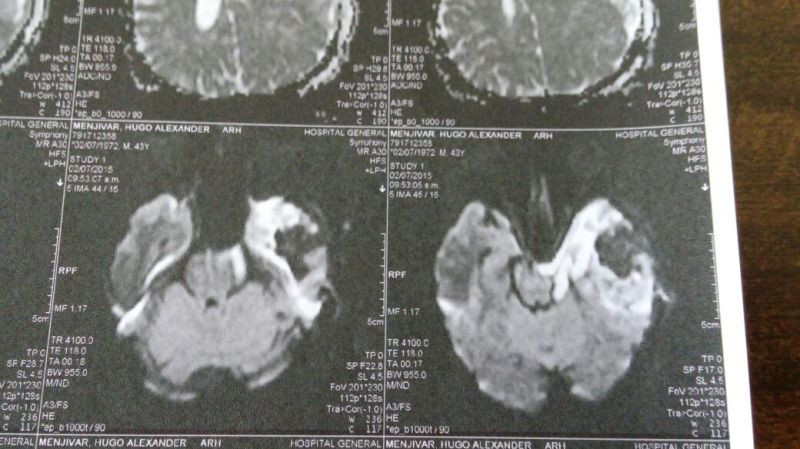

Oligodendroglioma temporal izquierdo Imagenes MRI Preoperatorio

Oligodendroglioma temporal Imagenes MRI Preoperatorio